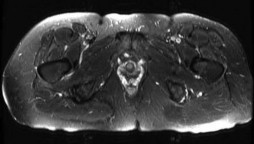

Question 5:

A 24-year-old collegiate hockey player presents with persistent anterior groin pain exacerbated by hip flexion and internal rotation. Radiographs demonstrate an alpha angle of 72 degrees on the Dunn view. Which of the following best describes the primary pathomechanical pattern of chondral damage associated with this morphology?

Options:

- Global full-thickness chondrolysis of the femoral head

- Contrecoup cartilage lesions in the posteroinferior acetabulum due to levering

- Delamination of the anterosuperior acetabular cartilage due to outside-in shear forces

- Crushing of the labrum with secondary ossification of the acetabular rim

- Ligamentum teres avulsion leading to medial joint space narrowing

Correct Answer: Delamination of the anterosuperior acetabular cartilage due to outside-in shear forces

Explanation:

An alpha angle > 55 degrees indicates Cam-type femoroacetabular impingement (FAI). Cam morphology causes outside-in shear forces against the anterosuperior acetabular rim during hip flexion and internal rotation. This selectively damages the transitional zone cartilage, causing delamination of the articular cartilage off the subchondral bone while often leaving the labrum initially intact. Pincer impingement typically causes labral crushing and contrecoup chondral lesions.